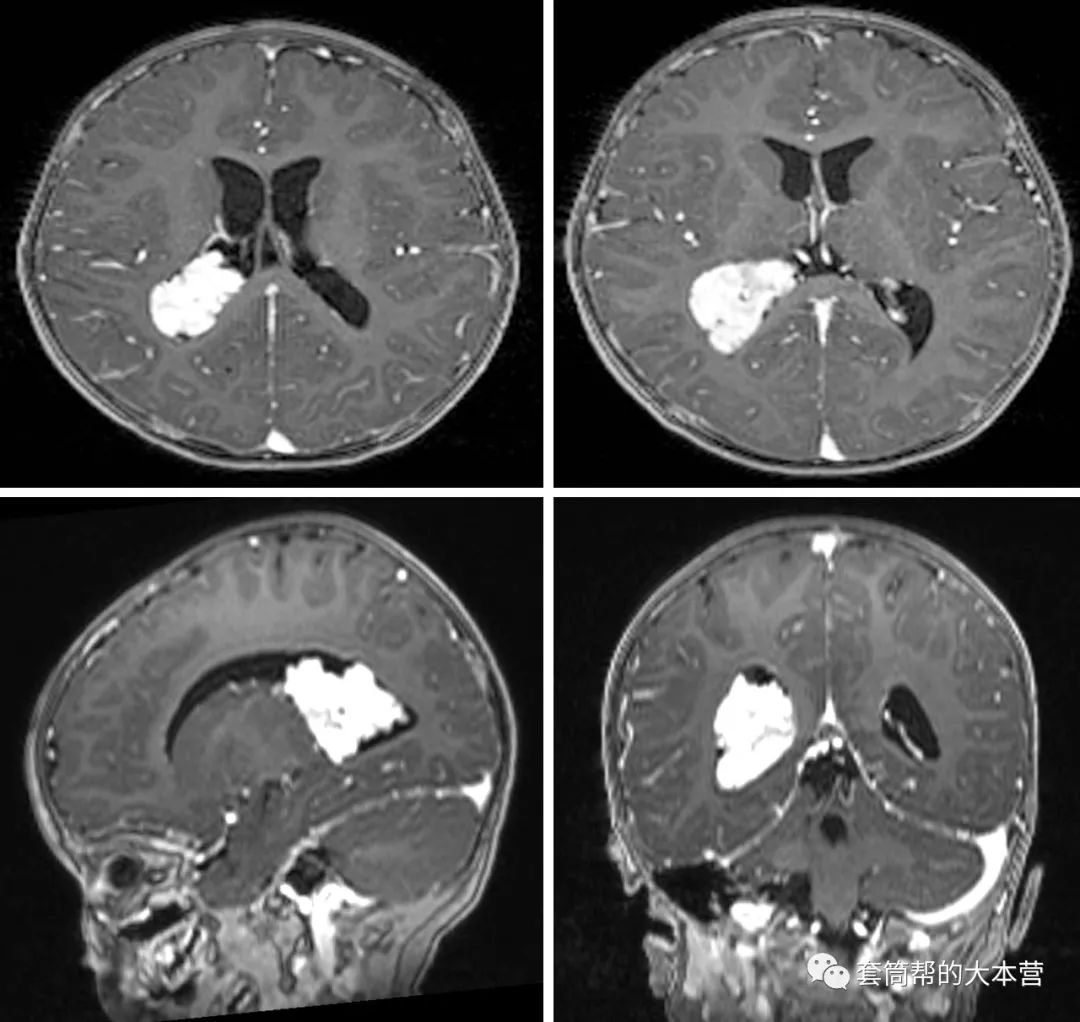

话说,这个小家伙年方1岁6个月,近几个月总是哭闹,家长带去做了个磁共振,结果祸事来了,发现颅内长了个大瘤子。

这是右侧脑室三角区的一个大瘤子,而且增强很明显,说明肿瘤的血供很丰富。结合小宝宝的年龄和肿瘤的影像学特点,考虑肿瘤是脉络丛乳头状瘤的可能性很大。各位看官知道,脑室内肿瘤属于脑深部肿瘤,常规开颅手术创伤较大,有较高的并发症的发生率。据文献报道,脑室内肿瘤术后早期发生严重并发症,并需要再次进行外科手术的几率高达11.5%(参考文献1)。这病例肿瘤大,位置深,本身就已很困难,加上病人年龄小(1岁6个月),对手术创伤和失血的耐受性很差。这就要求,必须以较小的创伤,很少的失血,安全地把这深部大瘤子给切了。这可如何是好?